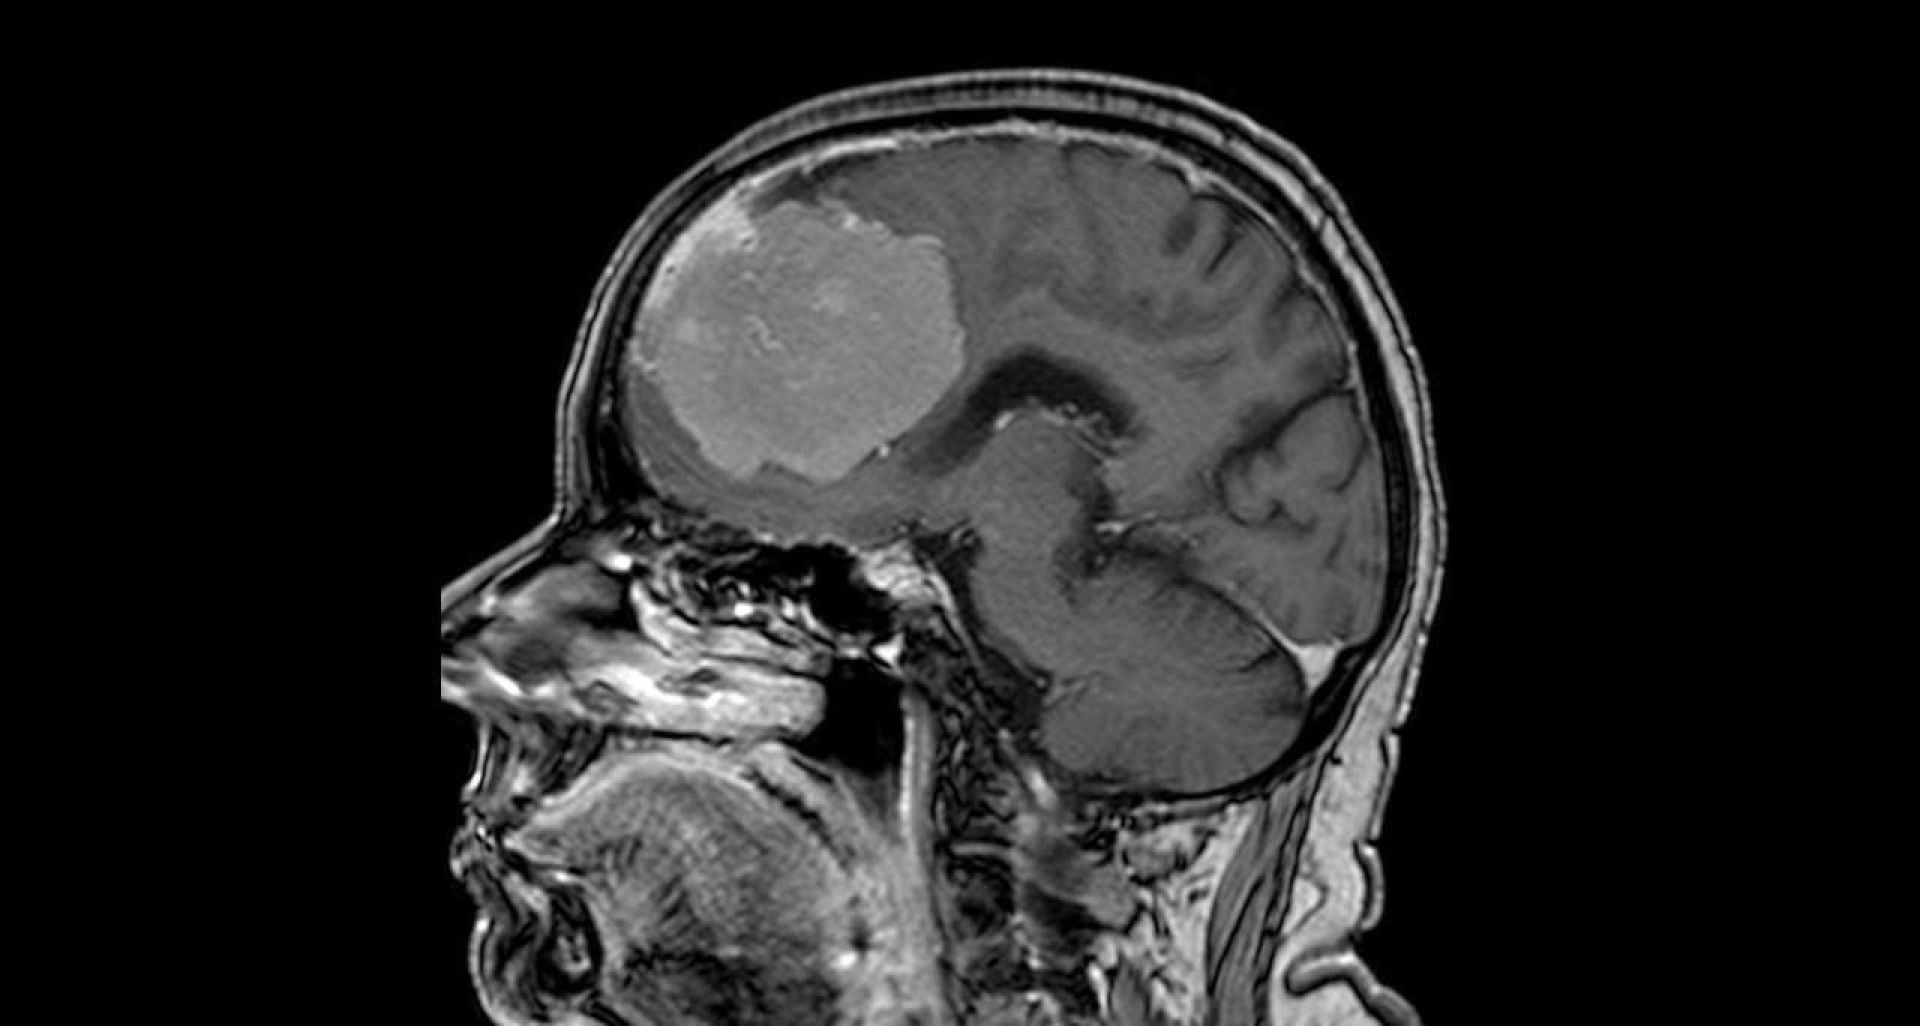

Воронежанке удалили опухоль головного мозга размером с грейпфрут, сообщили в БСМП № 1.

80-летняя женщина попала с больницу с подозрением на инсульт. У неё были проблемы с речью и слабость в правой руке. Этого недуга у женщины не обнаружили, однако после МРТ стало понятно, что причина недомогания кроется в гигантской опухоли, которая располагается на обеих лобных долях мозга и давит на крупные артерии.

Врачи назначили пациентке операцию. Важно было не только избавиться от новообразования, но и не повредить артерии и сосуды. Вмешательство длилось шесть часов, нейрохирурги Павел Юров и Виталий Бойко удаляли опухоль миллиметр за миллиметром. В итоге операция завершилась успешно.